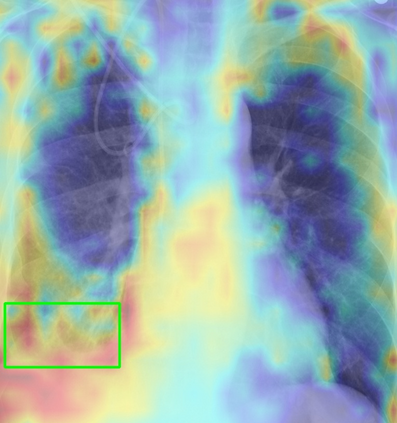

Tuberculosis remains a critical global health issue, particularly in resource-limited and remote areas. Early detection is vital for treatment, yet the lack of skilled radiologists underscores the need for artificial intelligence (AI)-driven screening tools. Developing reliable AI models is challenging due to the necessity for large, high-quality datasets, which are costly to obtain. To tackle this, we propose a teacher--student framework which enhances both disease and symptom detection on chest X-rays by integrating two supervised heads and a self-supervised head. Our model achieves an accuracy of 98.85% for distinguishing between COVID-19, tuberculosis, and normal cases, and a macro-F1 score of 90.09% for multilabel symptom detection, significantly outperforming baselines. The explainability assessments also show the model bases its predictions on relevant anatomical features, demonstrating promise for deployment in clinical screening and triage settings.